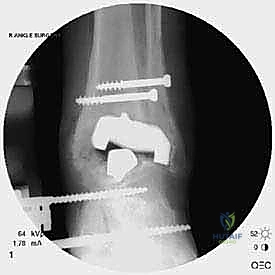

- الأشعة السينية مع تحميل الوزن (Weight-bearing X-rays): لتقييم الزوايا الميكانيكية وتحديد مدى هبوط المفصل أو وجود كسور في الكعب.

* دمج الكاحل (Ankle Arthrodesis): إذا كان التآكل العظمي هائلاً ولا يسمح بتركيب مفصل جديد، يتم إزالة المفصل الصناعي ودمج عظمة الساق مع عظمة الكاحل باستخدام مسامير وصفائح معدنية وطعوم عظمية.

علاج هذه الكسور يتطلب مهارة فائقة من الدكتور محمد هطيف، حيث يتم استخدام تقنيات الجراحة الميكروسكوبية وتثبيت الكسور باستخدام صفائح معدنية دقيقة ومسامير (Locking Plates) دون المساس بثبات المفصل الصناعي، أو يتم دمج علاج الكسر ضمن عملية مراجعة المفصل الكلية إذا كان المفصل نفسه تالفاً.

يتم إدخال المفصل الجديد المخصص للمراجعة، والذي يحتوي غالباً على سيقان (Stems) تدخل عميقاً في عظمة الساق وعظمة الكاحل لضمان الثبات الميكانيكي. في حال وجود كسور في الكعب، يتم تثبيتها في هذه المرحلة.